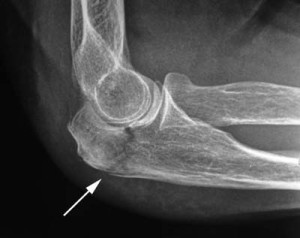

Диагностика

Без диагностики лечение не назначается, так как можно перепутать перелом с другими видами травм. Также необходимо определить, повреждены ли сосуды и нервы. После тщательной диагностики лечение подбирается индивидуально.

При подозрении на перелом локтевого сустава, немедленно обратитесь к врачу. Самостоятельная диагностика может привести к неправильному лечению и ухудшению состояния. Врач проведет необходимые обследования, такие как рентген, для точного определения характера травмы.